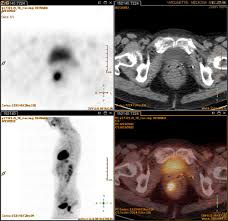

A pet scan is not specific for cancer. It also can let you and your doctors know if cancer treatment is working. The scanner detects diseased cells that absorb. With that being said, not all cancers can be detected by pet. A pet scan, which uses a small amount of radioactive material, can help show if an enlarged lymph node is cancerous and detect cancer cells throughout the body that may not be seen on a ct scan. Positron emission tomography (pet) imaging scans use a radioactive tracer to check for signs of cancer, heart disease and brain disorders. The pet scan detects the concentrated psma tracer, pinpointing these tumors for more effective treatment. Psma pet imaging is a fda approved scan with more precise detection of prostate cancer for better treatment planning and targeted care. Most pet scans use a type of radiolabeled sugar to detect the cancer, as the majority of cancers grow quickly and need sugar for that growth. Pet can detect extremely small cancerous tumors, subtle changes of the brain and heart, and give doctors important early although cancer spreads silently in the body, pet can inspect all organs of the body for cancer in a single examination. Pet scans, short for positron emission tomography, can detect areas of cancer by obtaining images of the body's cells as they work. Ultrasound is also used to image the abdominal organs and kidneys. To determine whether the cancer has spread.

Scheduled to get a pet scan? Because of this high level of chemical activity, cancer cells the combined use of pet scans and ct scans is an effective method for detecting pelvic recurrences of rectal cancer. Prostate cancer that spreads or comes back after treatment is often small and hard to detect. For cancer and disease detection, the most commonly used nuclear scan is an fdg pet scan. Nuclear medicine images use a small quantity of a radioactive substance to detect, evaluate, or treat various diseases.

Pet Ct For Prostate Cancer From Diagnosis To Metastasis Renal And Urology News from www.renalandurologynews.com The pet scan detects the concentrated psma tracer, pinpointing these tumors for more effective treatment. Most pet scans use a type of radiolabeled sugar to detect the cancer, as the majority of cancers grow quickly and need sugar for that growth. Possible risks of a pet scan. A pet scan is not specific for cancer. Cancer patients and their doctors now have access to a superior imaging technology in pet scans. A pet scan shows how your tissues and organs are functioning. Pet/ct method has no competitors in oncology that could equally detect: Any exposure to radiation carries a very small risk of potential tissue damage that could cause cancer at a later date.